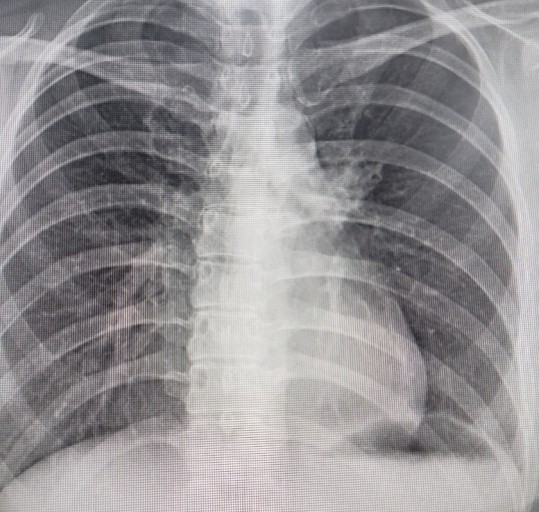

9. 흉부 고통

폐암에 걸리면 흉부에 고통이 느껴져요. 폐의 가장자리에 생긴 폐암이 흉막과 흉벽을 침범해서 고통이 생기는 것으로 가슴이 답답하면서 꽉 막힌 느낌이 지속되며 날카롭게 찌르는 듯한 느낌과 압력 하는 느낌 등 여러 가지 고통이 나타납니다.

폐암 초기증상 10. 상체 전반적인 고통

흉부 고통뿐 아니라 폐에 암세포가 상체 쪽으로 전이될 그럴 경우 상체 여러 곳곳에서 고통을 느낄 수 있어요.